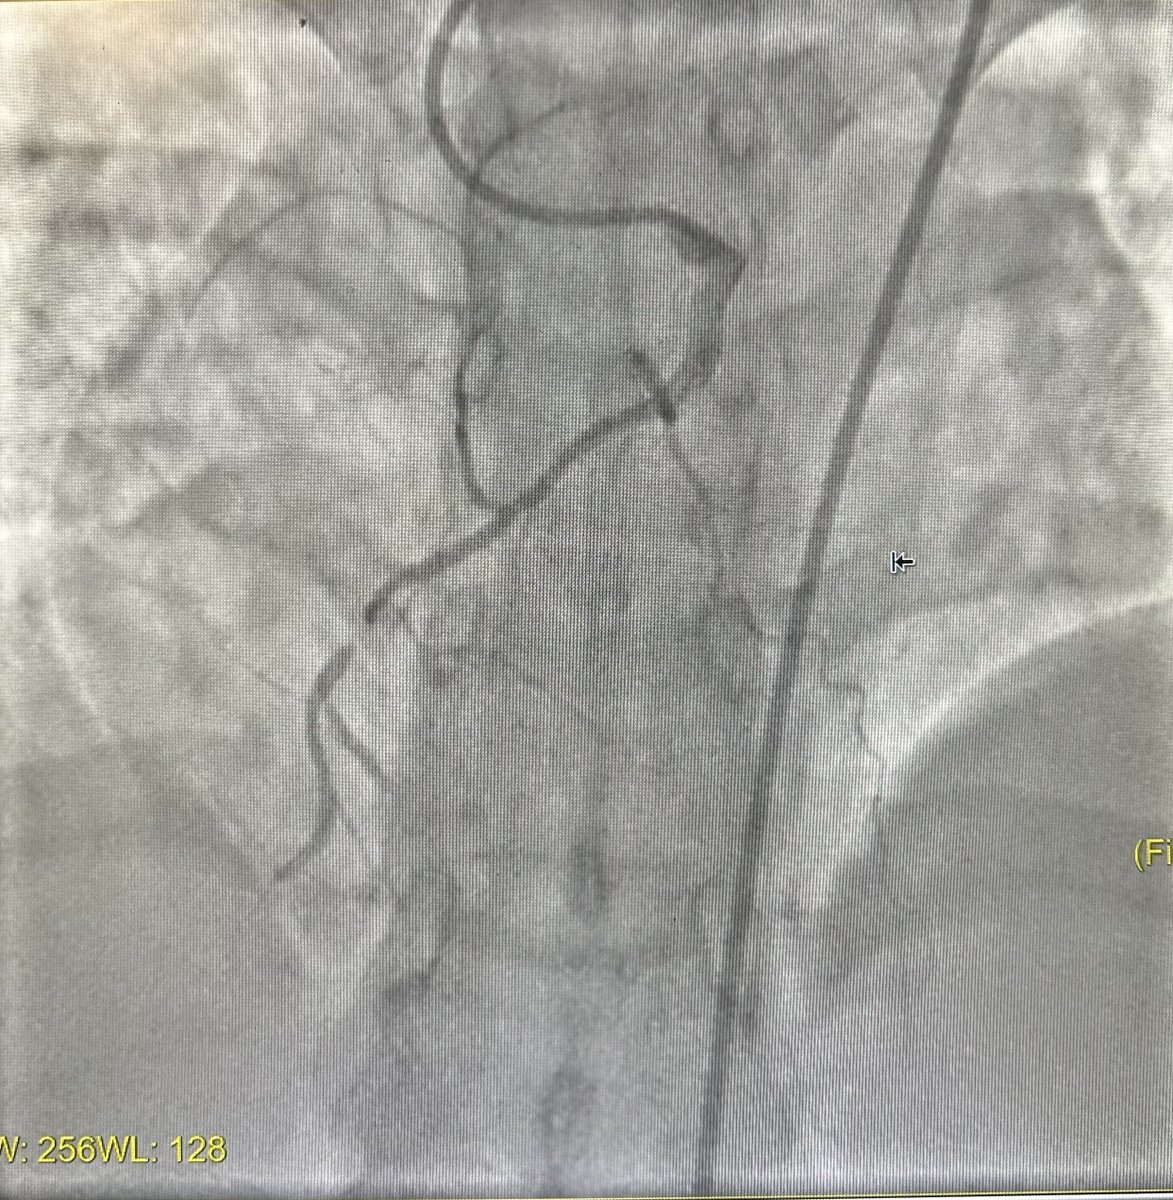

Antegrade CTO Intervention of RCA. “Simple approach”. Single access / Single CTO wire / Single MC. Blunt/Calcium/Angulation/Antegrade filling from ipsilateral collaterals. #CTO101 #ICFIT

evandrofilhobr's tweet image. Antegrade CTO Intervention of RCA. “Simple approach”.

Single access / Single CTO wire / Single MC.

Blunt/Calcium/Angulation/Antegrade filling from ipsilateral collaterals. #CTO101 #ICFIT